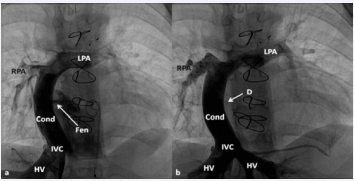

Figure 34 Selected cine frames in postero–anterior (a) and lateral (b) views, demonstrating Stage IIIA Fontan procedure diverting the inferior vena caval (IVC) flow into the pulmonary arteries via a nonvalved conduit (Cond). Flow across the fenestration (Fen) is shown by arrows in a and b. HV, hepatic veins; LPA, left pulmonary artery; PG, pigtail catheter in the descending aorta; RPA, right pulmonary artery [82].